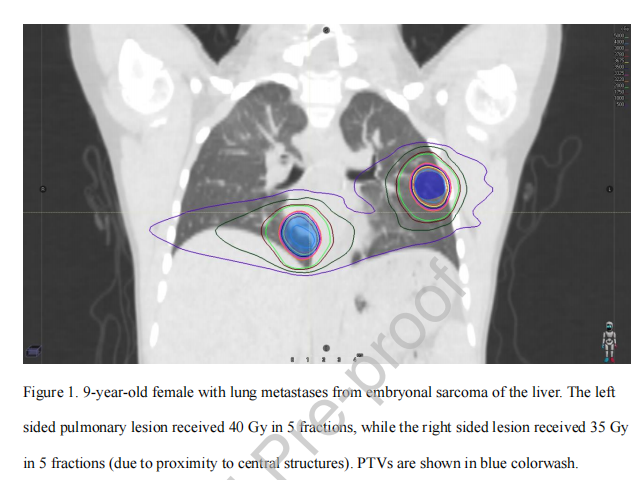

前瞻性和回顾性数据均支持SBRT对儿童和年轻人的安全性和局部有效性。表1总结了选定的大型研究。Singh等对儿童SBRT的研究进行了综合荟萃分析,他们评估了9项研究,共142例患者和217例病变。最常见的病变部位是脊柱或脊柱旁(83例)、非脊柱骨(72例)和肺(53例),而最常见的组织学是骨肉瘤(45例)、尤文氏肉瘤(43例)、其他软组织肉瘤(20例)和神经母细胞瘤(10例)。值得注意的是,他们发现生物效应剂量(BED) (α/β = 10)每增加10Gy, SBRT治疗后2年局部控制提高5%。立体定向放射治疗肺部病变是可行的;图1提供了一个示例。有趣的是,在一项双中心系列回顾性研究中,与骨转移相比,SBRT治疗的软组织病变具有较差的局部控制,这可能是由于需要尊重附近内脏OARs的剂量限制。在47例因转移而出现症状的患者中,62%的患者通过SBRT获得了临床改善。

图1。 19岁女性,肝胚胎性肉瘤肺转移。左侧肺病变接受5次40 Gy,(由于靠近中心结构)右侧病变5次接受35 Gy的照射。TV显示为蓝色。表1.颅外SBRT在儿童和年轻人中的选择性研究。